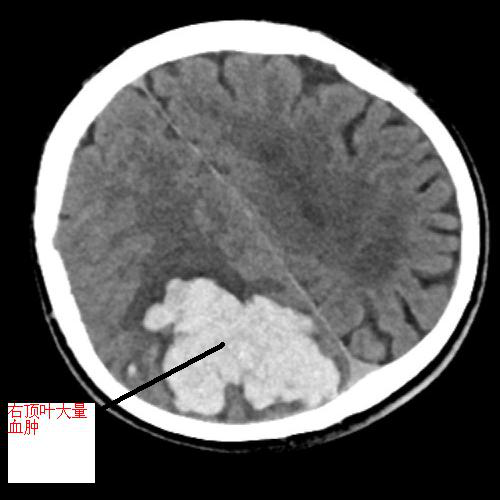

黃阿伯,現(xiàn)年60歲,9月中旬被發(fā)現(xiàn)躺于地上,言語(yǔ)不能、反應(yīng)遲鈍、左側(cè)肢體無(wú)力,緊急送至我院急診科,考慮右頂葉出血破入腦室,出血量超90ml,出血量大,周圍腦溝腦回、右側(cè)腦室受壓,呈嗜睡狀態(tài),有急診手術(shù)指征。不進(jìn)行手術(shù)后續(xù)水腫出現(xiàn)及加重、顱內(nèi)壓力增加、占位效應(yīng)加重,將進(jìn)一步損害腦組織。

術(shù)中,見手術(shù)視野壓力高,腦組織受壓,黃金鐘主任給予內(nèi)鏡下充分清除血腫、止血,見腦組織壓力減低,腦血管搏動(dòng)有力。

▲左圖為術(shù)前顱內(nèi)血腫,右圖為手術(shù)后原血腫位置,血腫已基本清除